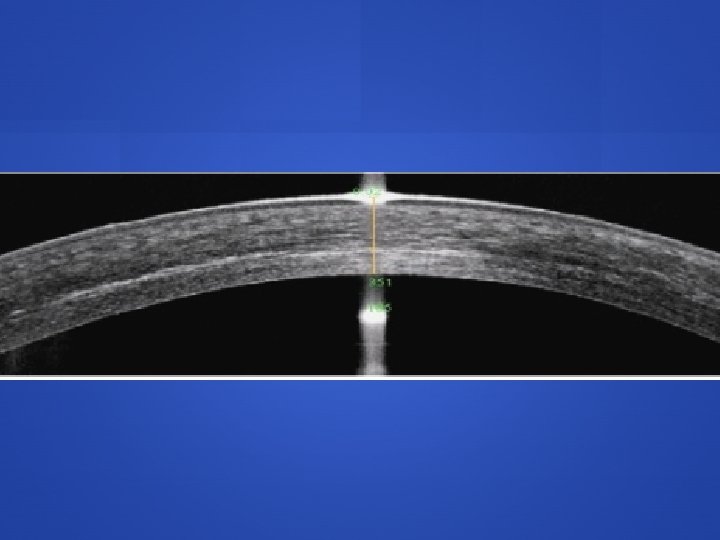

Epi-On vs. Epi-Off Efficacy of epi on vs epi off highly debated Far fewer transepithelial studies: 10 -15 many show similar ability to halt progression as epi off However 3 studies with significant corneal steep, 1 study with a 50% retreatment rate (higher than any epi off study) CXL demarcation line depth on OCT 140 to 250 um (epi on) vs 280 to 330 (epi off) A RCT head to head comparison will be required

Current Crosslinking FDA-approved epi-off protocol Approved for KCN (April 2016) and post LASIK ectasia (July 2016) Epithelial debridement Photrexa and Photrexa Viscous (Avedro) 30 minute application Avedro KXL System: 365 nm UVA light with power of 3 m. W/cm 2 for 30 minute treatment